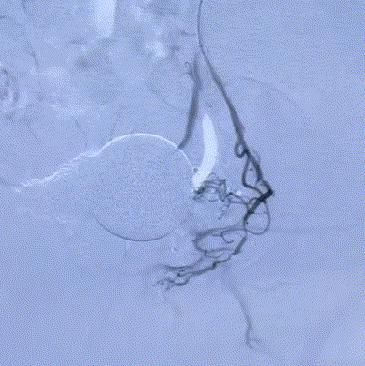

随後,李旭丹主任攜手胡志華主任爲患者實施介入治療,采用改良Seldinger法穿刺股動脈,在DSA引導下經動脈自然腔道,将微導管分别送達雙側髂内動脈進行造影,觀察雙側前列腺動脈分布情況,将微導管超選擇至雙側前列腺動脈,準确置入PVA栓塞材料,成功阻斷前列腺的營養供給,順利完成了治療。

△術後,前列腺供血動脈被成功阻斷。